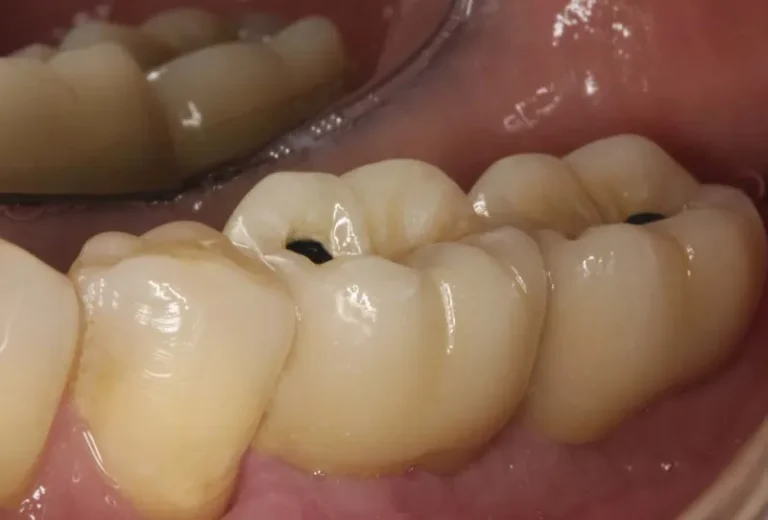

Si notas que tu implante dental se ha aflojado, es fundamental actuar con rapidez y contactar inmediatamente con tu dentista. Este problema puede deberse a diversos factores como infecciones, sobrecarga oclusal o pérdida ósea, y requiere atención profesional urgente para evitar complicaciones mayores. Mientras esperas tu cita, evita manipular el implante, mantén una higiene meticulosa…